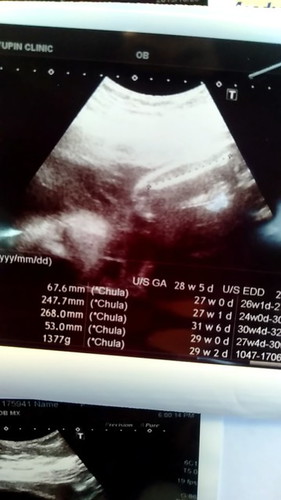

27w+3

ไปหาคุณหมอมาวันนี้ นน.ลูก 1377 กรัม แม่ไปว่า มากหรือน้อยไปคะ

น้ำหนักดีมากๆเลยค่ะแม่